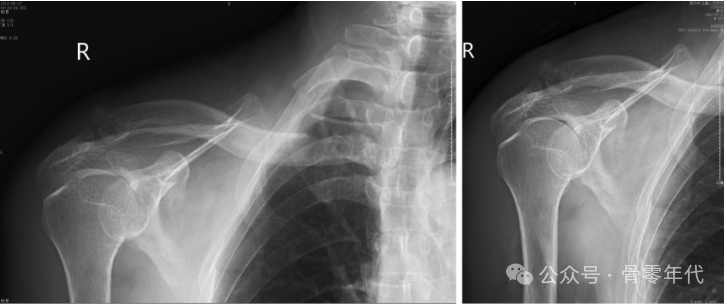

一名62岁的女性在当地医院接受了内侧和远端固定。她经历了持续的锁骨内侧突出和疼痛,术后1个月(A)后前位X线片和(B)三维CT显示锁骨内侧骨片再次移位。她接受了翻修手术,包括移除最初的植入物并用锁骨钩钢板固定。在6个月的随访中,患者显示胸锁关节和肩锁关节的X线片是一致的。